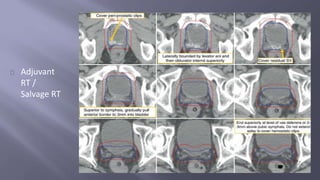

Adjuvant

RT /

Salvage RT

Indicated in adverse path features ; detectable PSA with no evidence of

disseminated disease

Usually given within 1 year after RP and once operative side effects are

minimized

Salvage therapy is indicated in detectable PSA that increases on 2 subsequent

occasions . Most effective if pre treatment PSA is < 1 ng /ml

Recommended dosage : 64 to 68 Gy in std fractionation

Defined target volume is the prostate bed

Inclusion of pelvic nodes can be considered but not necessary.